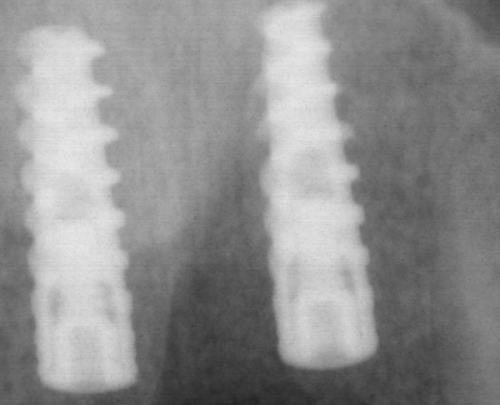

西安双宝口腔医院的设备齐全,拥有精良的口腔检查设备、治疗设备等。这些设备能够帮助医生更正确地诊断病情,制定更科学的治疗方案。例如,口腔CT设备可以清晰地显示牙齿和颌骨的内部结构,为种植牙、正畸等治疗提供重要的依据。在服务方面,医院始终坚持以患者为中 心,从患者进门的那一刻起,就有专精的导医为患者提供引导和帮助。在治疗过程中,医生和护士会耐心地解答患者的疑问,关心患者的感受,让患者在舒适的环境中接受治疗。治疗结束后,医院还会为患者提供详细的护理指导和回访服务,确保患者的口腔健康得到持续关注。